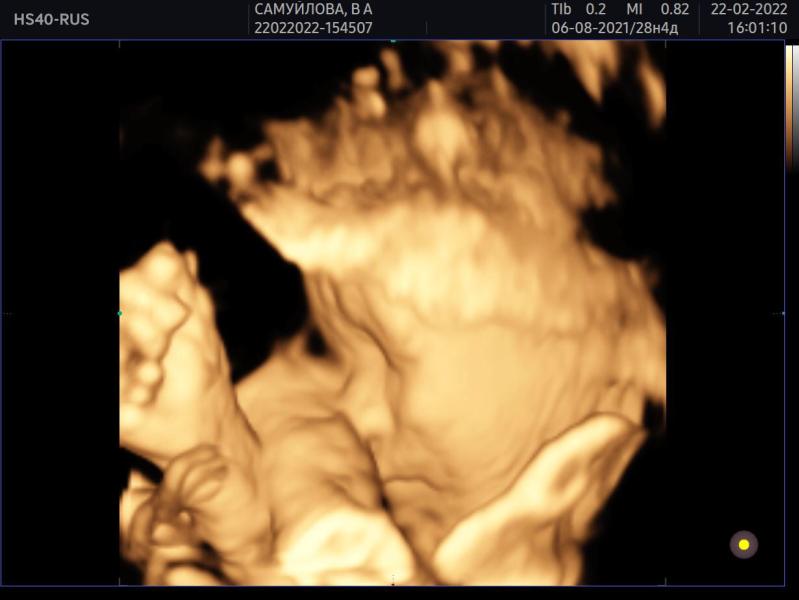

22.02.22 💙

Были на 3д узи

Срок 28 недель

Вес 1158 +_178гр

Чсс 157 уд/мин

Окружность головы 261мм

Окружность живота 240мм